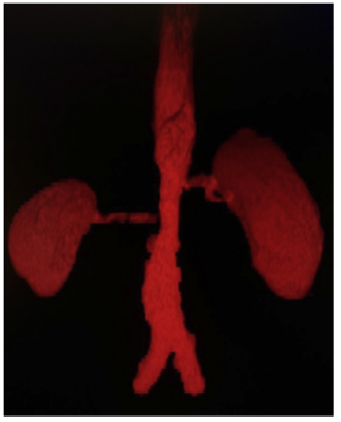

A 20-year-old Mexican male, with no relevant family history, began at age 16 with symptoms of pain and claudication in the lower extremities, fatigue, and elevated blood pressure levels. On physical examination, asymmetry of the popliteal and pedal pulses, abdominal bruit, and discrepancy of blood pressure values (>10mmHg) in upper limbs compared to lower limbs was observed. A secondary arterial hypertension approach was started; endocrinopathies were initially excluded. Hence, computed tomography angiography with three-dimensional reconstruction was performed (Fig. 1), in which 70% stenosis of the inframesenteric abdominal aorta involving both renal arteries at the level of the ostium was documented; supra-aortic trunks showed no lesions. An elevation of acute phase reactants (C-reactive protein 18.1mg/dl and erythrocyte sedimentation rate 64 mm/h) was found. With this information, TA classification criteria were met. Baseline renal function was preserved (serum creatinine: 0.58mg/dl and glomerular filtration rate: 146ml/min). Immunosuppressive treatment with steroids was started with prednisone at 50mg/day (1mg/kg/day), with a dose reduction to 20mg/day at 6 months follow-up and 5 mg/day after 12 months. In addition, methotrexate up to 15 mg/week, anticoagulation with rivaroxaban, and antihypertensive therapy with losartan and nifedipine were administered. In the third year of follow-up, there was an increase in serum creatinine; hematuria (20 red blood cells per high-power field), and albuminuria in the subnephrotic range (1441 mg in 24h) also were documented. A renal ultrasound is performed, evidencing normal morphology and size: right kidney 9.3 x 6.6 x 5 cm; left kidney 10.2 x 7.4 x 5.1cm in their longitudinal, anteroposterior, and transverse axes, respectively.

Figure 1 Abdominal aortic angiotomography with 3D reconstruction depicting stenosis of the adrenal portion at to the bifurcation, with stenosis of the renal arteries.